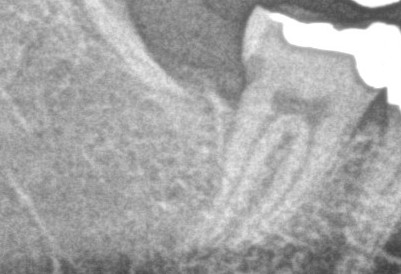

今回は藤沢の患者さまで右下第二大臼歯が親知らずのせいで虫歯になりMTAセメントを詰めたケースのご紹介です💡

こちらが処置前のPhotoとレントゲンになります

見た感じは問題なさそうですが、削っていくと虫歯はかなり深くまで進行していました